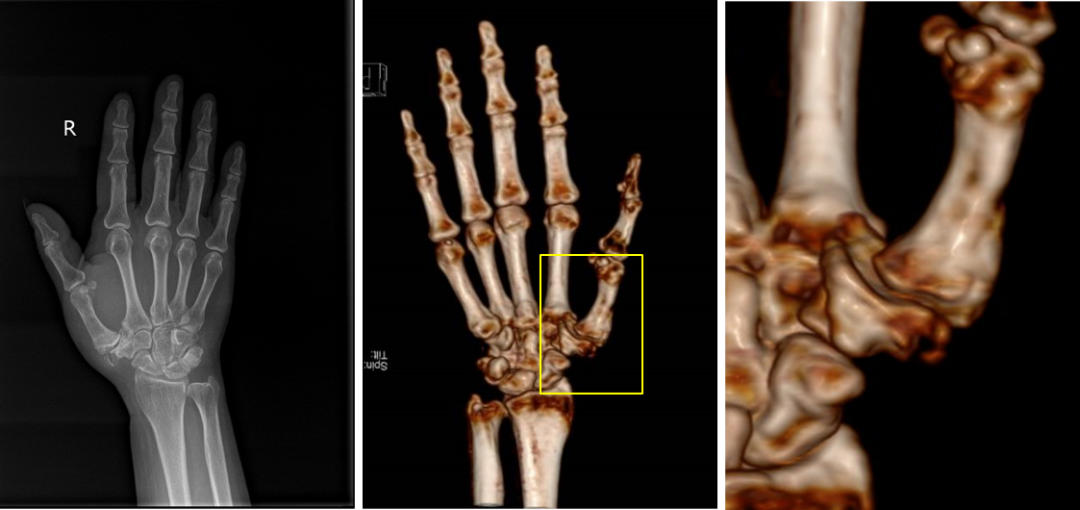

历经1个多小时的手术,患者的右手第一腕掌关节被全新的人工假体所代替。术后拍摄x线检查,假体摆放位置精确,与术前规划完美匹配。患者术后1个月来院复查时关节周围无明显红肿,疼痛感较术前明显改善,关节功能恢复正常水平。

△术后1个月患者右手第一掌指关节康复良好